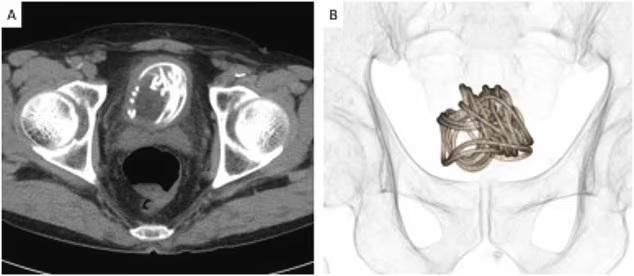

報道指,日本去年11月一個案更加嚇人,一名79歲老翁將90吋長的跳繩塞入陰莖,結果在膀胱內打圈塞住。由於要取出的難度極高,醫生甚至要靠電腦3D圖模擬如何在膀胱開刀取出跳繩。雖然老翁並沒有向醫生解釋為何塞繩入陰莖,但相信他是為了性快感。有英國醫生說,這是他聽過最極端的個案。